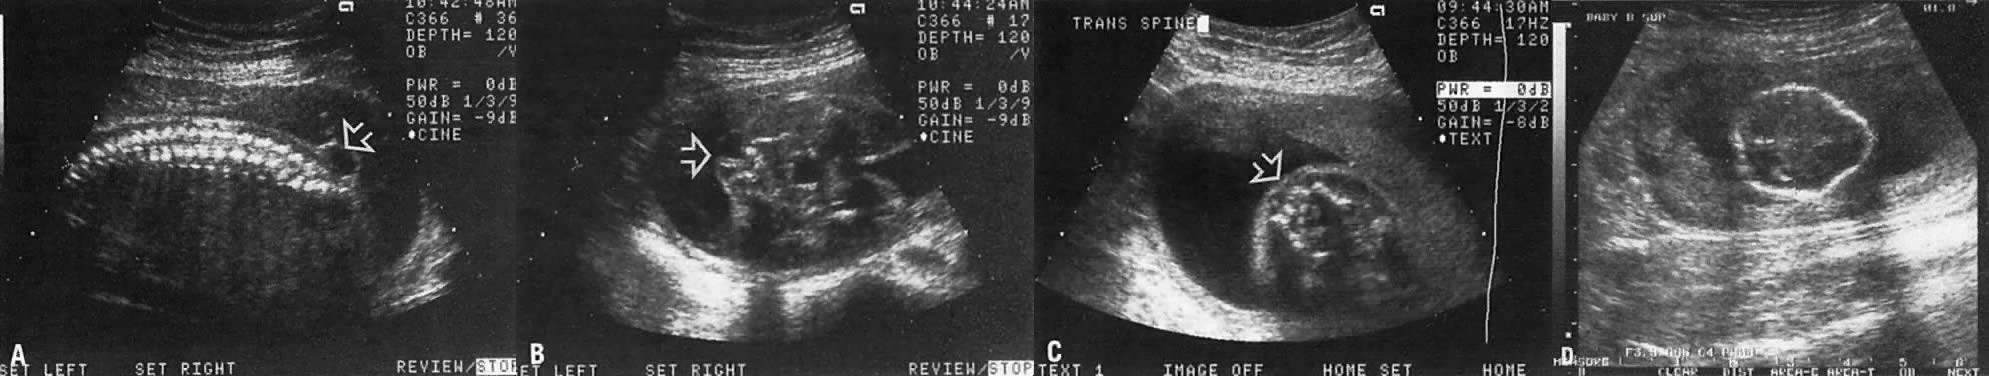

Spina bifida is frequently associated with meningocele. The latter represents extrusion of the meninges through the bony defect. Some cerebrospinal fluid (CSF) is usually contained within the meningocele. As a result, the area appears cystic, an ultrasound characteristic that enhances visibility of small spina bifida (Fig. 21).

Fig. 21. A. Longitudinal scan fetal spine. Note meningocele in the lumbosacral area (arrow). B. Cross-sectional view of the fetal lumbosacral area shows open spina bifida covered by a meningocele (arrow). C. Cross-sectional view of normal lumbosacral area showing rounded closed spin covered with skin (arrow). D. Echogram of fetal head with spina bifida, showing the lemon sign (i.e., scalloping of the frontal bones of the fetal head.

In spina bifida, splaying of the spine is noted in the longitudinal plane. However, small spinae bifida located in the lumbosacral area are best visualized by careful cross-sectional imaging (see Fig. 21). The size of spinae bifida varies from a tiny bone defect to one involving many segments of the spine (myeloschisis).

Importantly, an Arnold-Chiari type II malformation occurs in nearly all cases of spina bifida. This is characterized by forward scalloping of the frontal aspect of the fetal head (lemon sign; see Fig. 21), and an abnormal, banana-shaped cerebellum (banana sign). The ultrasonographer should always look for these signs during the examination; if they are present, the ultrasonographer should extend the examination to search for spina bifida.80